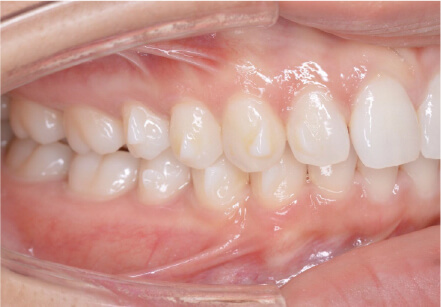

叢生の症例

41歳

/

女性

相談内容

横から見た時のガタガタが気になる

カウンセリング・診断結果

インビザライン、正中は上11に合わせていく、抜歯・拡大装置・IPR・アタッチメントOK

治療内容・方法

アライナー矯正

術後の経過・現在の様子

クリアライナー使用

治療のリスク

痛み・歯根吸収・歯肉退縮・虫歯・後戻り

費用・治療期間

880,000円、7ヶ月

トレーニングなど